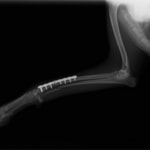

症例3:キルシュナーワイヤーのピンニングによる整復

ペルシャ猫 11ヶ月齢 雄

他院にて左大腿骨遠位の成長板骨折(salter-harrisⅠ型)が認められており、治療相談を目的として来院。当院にて、キルシュナーワイヤーを用いたピンニングにより骨折部位の整復を行いました。術後の経過は良好で、現在も経過観察中です。

術前レントゲン

術後レントゲン